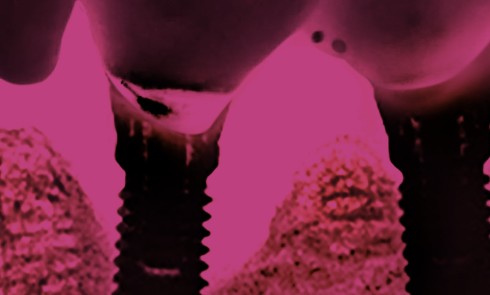

Implantologie

Article réservé à nos abonnés Le traitement des péri-implantites

Coordination scientifique : Philippe Khayat, Benjamin Pomès Dans cette édition spéciale, onze articles et 17 auteurs font le point sur...